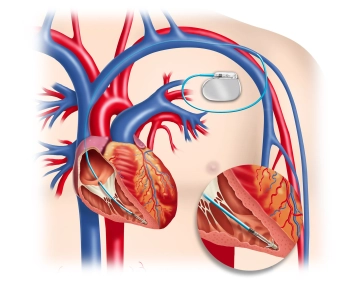

Cavidades internas

Mediante septos, el corazón se divide verticalmente en una mitad derecha e izquierda, horizontalmente en un atrio (atrio) y un ventrículo (ventrículo) respectivamente. De esta forma, resultan cuatro cavidades cardíacas:

- Atrio derecho (Atrium cordis dextrum)

- Ventrículo derecho (Ventrículo derecho, Ventriculus cordis dexter)

- Atrio izquierdo (Atrium cordis sinistrum)

- Ventrículo izquierdo (Ventrículo izquierdo, Ventriculus cordis sinister)

La dirección del flujo sanguíneo se regula mediante cuatro válvulas cardíacas de manera similar a una válvula:

- Válvula tricúspide entre atrio der. y ventrículo der.

- Válvula pulmonar entre ventrículo der. y la arteria pulmonar

- Válvula mitral entre atrio izq. y ventrículo izq.

- Válvula aórtica entre ventrículo izq. y aorta

Endocardiorecubre toda la superficie interna del corazónlas válvulas cardíacas son prolongaciones a